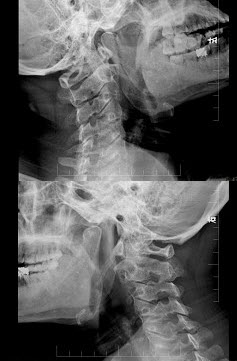

- 多项选择题37岁,女性患者,咽部异物感、咽痛伴反射性耳痛、头颈部不适近一年余,X线检查如图所示,请选择正确的描述和答案()。

A、左侧茎突长约3.5cm

B、右侧茎突长约4.0cm

C、双侧茎突过长综合征

D、右侧茎突过长综合征

E、正常茎突

- A,B,C